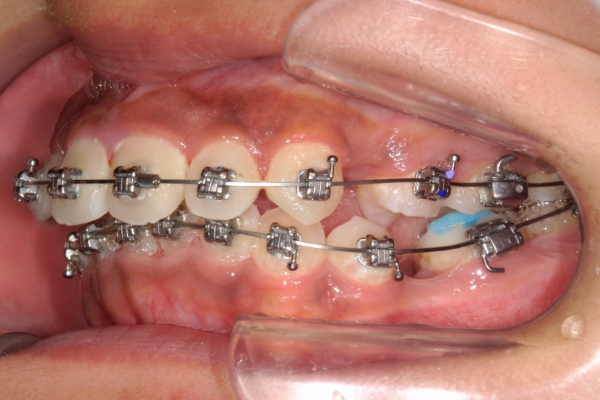

PROCESS

半年

上顎前歯が1cm近く前方に出ており、叢生を改善しつつ前歯を大きく引っ込めるために上下顎小臼歯の抜歯が必要と診断しました。治療後は、主訴であった前歯の突出と奥歯の噛み合わせのずれが改善され、上下の咬合関係が安定しました。